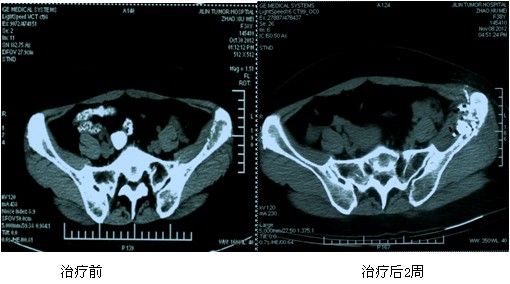

典型病例:赵XX,女,38岁,原发性肝右叶癌(BCLC C期)、多发性骨转移癌。左侧髋部及第4腰椎发现转移,左髋部疼痛明显,腰背部疼痛明显。给予125I放射性粒子植入及骨水泥局部填塞治疗后疼痛症状明显减轻,病灶明显萎缩。